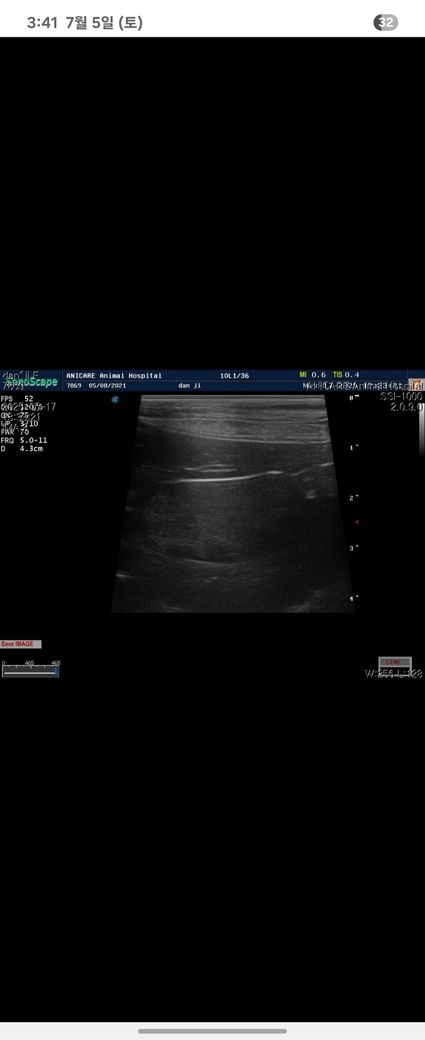

4살 강아지

건강검진에서 담낭슬러지를 발견했어요

어린데 담낭슬러지가 심하다고